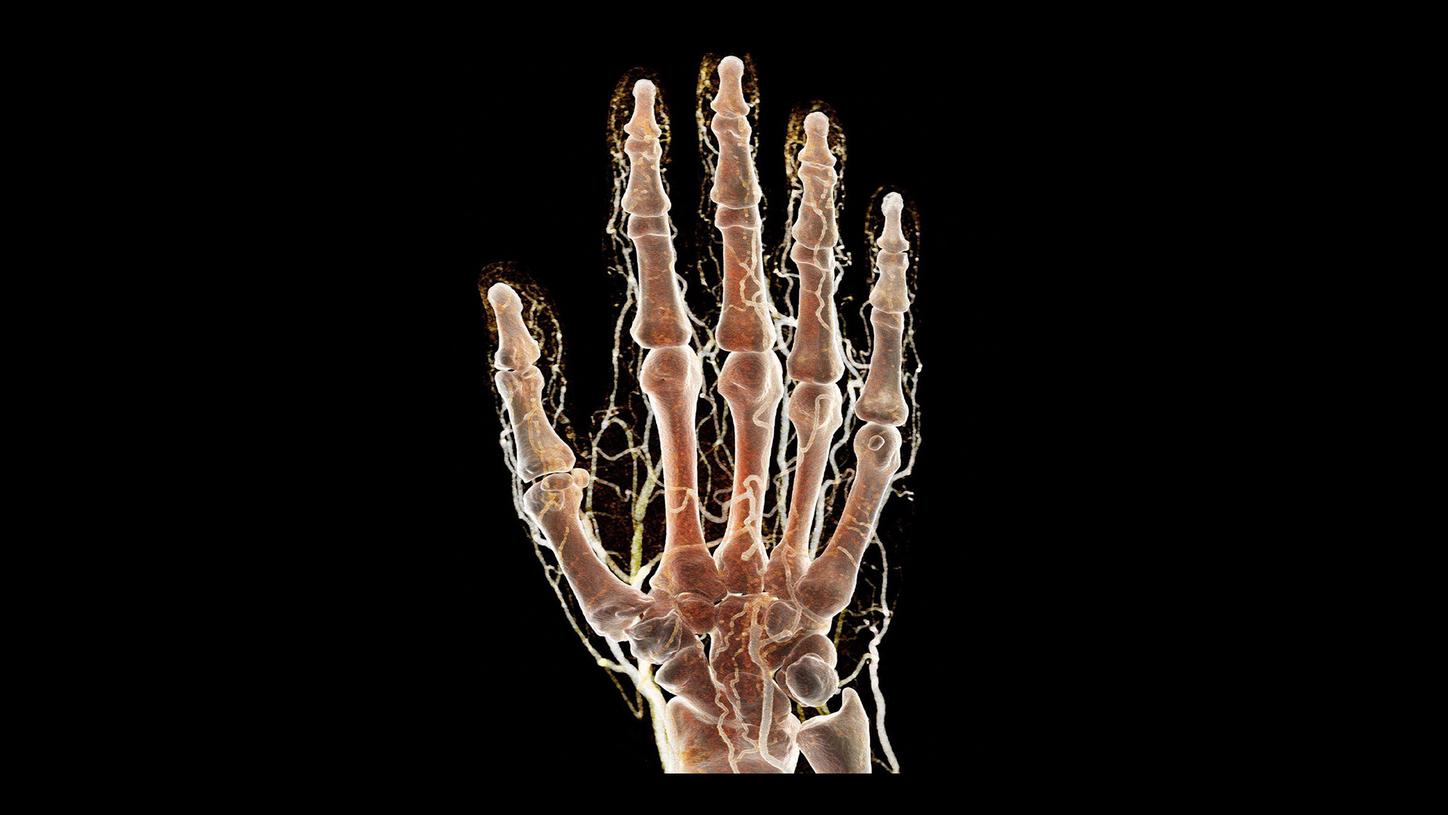

At the heart of NAEOTOM Alpha® is a radically new photon-counting detector. The QuantaMax detector directly converts X-rays into an electrical signal, which is then used to create an image. The energy of each X-ray is measured, so spectral information is available for every scan, and the images are contrast-rich with high spatial resolution at the same dose. Combining the high spatial resolution of the QuantaMax photon-counting detector with our Dual Source temporal resolution enables the visualization of fine details for increased diagnostic confidence.